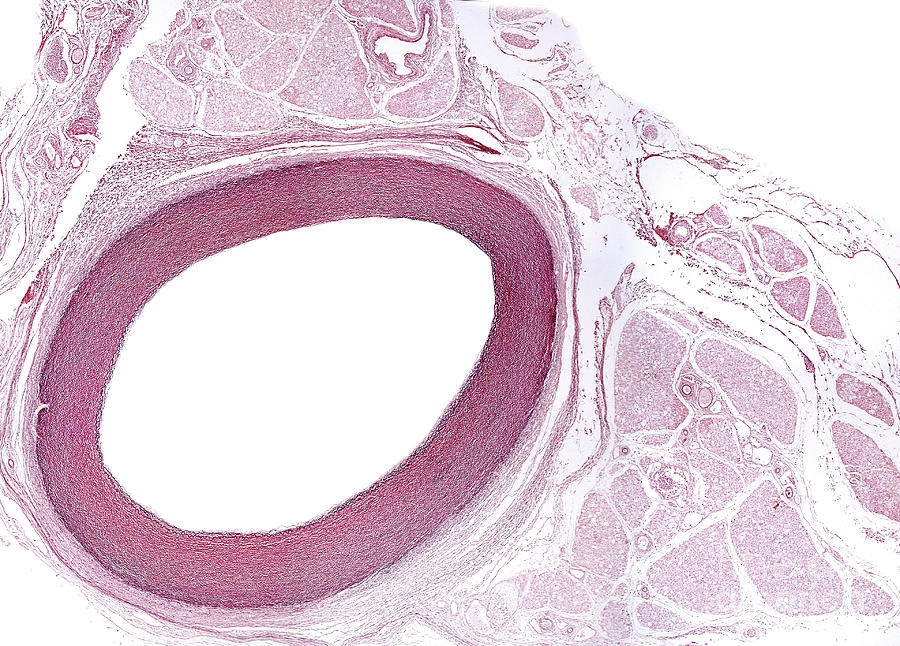

Elastic Artery Example . An elastic artery is also known as a conducting artery, because the large diameter of the lumen gives it a low resistance and enables it to accept a large volume of blood. They stretch and recoil in response to blood flow, maintaining constant pressure. The two types of arteries are: Have more elastic tissue than muscular arteries and are located close to your heart. Large arteries, also known as elastic arteries, examples of large arteries include the aorta and the pulmonary arteries. Elastic arteries are the largest arteries in the body, closest to the heart, with high elastic tissue content. The former is a wavy band of elastic fibers. The main difference between elastic and muscular arteries is that elastic arteries occur closest to the heart, experiencing a great pressure while the heart forces. The tunica intima of the large arteries is quite thick.

Elastic Artery 5 Photograph by Jose Calvo / Science Photo Library Pixels